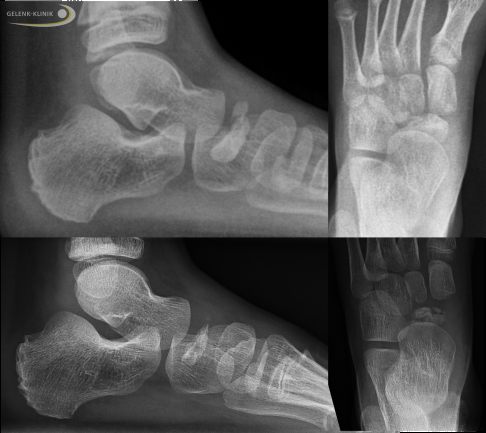

Die Röntgenaufnahmen zeigen bei fortgeschrittenem Müller-Weiss-Syndrom ein abgeflachtes Kahnbein, dass zunehmend nach innen (medial) und Richtung Fußrücken (dorsal) verdrängt wird. Das Kahnbein kann wie ein Komma erscheinen. Durch den Umbau (Sklerosierung) des abgestorbenen Knochenbereichs erscheint das Kahnbein auf der Röntgenaufnahme deutlich dichter und kompakter. In frühen Stadien der Erkrankung ist die Röntgenuntersuchung nicht hilfreich, da die knöchernen Veränderungen noch nicht sichtbar sind.

Erscheinungsform des Müller-Weiss-Syndroms: Sklerosierung des Kahnbeins und Ausbildung einer Komma-Form und Verlagerung des Kahnbeins zum Fußrücken aus seiner normalen Position (dorsalseitige Subluxation). © Gelenk-Klinik

Die Röntgenbilder zeigen eine nicht entzündliche (aseptische) Knochennekrose des Kahnbeins am Fuß, die nur bei Kindern vorkommt: Morbus Köhler I. Der Kahnbeinknochen ist zu klein und verformt. Die übrigen Fußknochen sind altersentsprechend entwickelt. Die großen Abstände zwischen den einzelnen Fußknochen entsprechen den noch knorpeligen Wachstumsbereichen. © Gelenk-Klinik

Die Röntgenbilder zeigen ein zweigeteiltes Kahnbein (Os naviculare bipartitum) am Fuß einer jugendlichen Patientin. Die defekte Form des Kahnbeins ähnelt der bei Müller-Weiss-Syndrom. Die knöchernen Strukturen zeigen radiologisch allerdings keine Osteonekrose und Sklerosierung des Kahnbeins. © Gelenk-Klinik